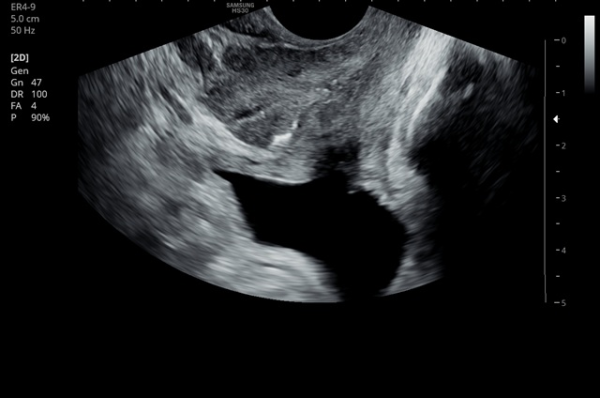

내원 첫 당일 경직장 전립선 초음파 검사상 사정관 입구의 결석들과 사정관 낭종이 관찰되는 사진입니다.(NIH:24)

On the initial transrectal prostate ultrasound, the image shows the presence of calcifications (stones) at the opening of the ejaculatory duct as well as a cystic lesion within the ejaculatory duct (ejaculatory duct cyst).(NIH:24)

주 2회 14주 동안 전립선과 정낭, 사정관과 정관등의 표적 치료후 사정관의 낭종등이 치료 되고 있는 경직장 전립선 초음파 검사 자료 입니다.(NIH:13)

This transrectal prostate ultrasound image shows improvement of an ejaculatory duct cyst after targeted treatment of the prostate, seminal vesicles, ejaculatory ducts, and vas deferens.

The treatment was performed twice a week over a period of 14 weeks. As a result, the previously noted cyst in the ejaculatory duct is gradually resolving, indicating improved drainage and recovery of normal ductal circulation.(NIH:13)

For the patient, this means that small stones and a cyst are blocking the natural passage where semen normally flows. These findings can explain symptoms such as pelvic pain, difficulty with ejaculation, blood in semen, or infertility.

Treatment may involve addressing these blockages to restore normal flow and relieve associated symptoms.